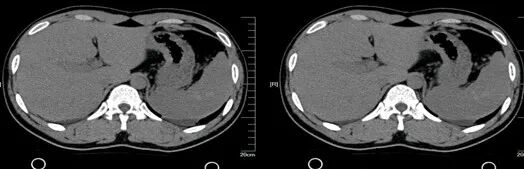

脾挫裂伤

病因病理

脾挫裂伤主要是指腹部受到外在力量的撞击而产生的闭合性损伤,是常见的腹部严重创伤,多由高处坠落、交通意外等引起。

临床表现

患者可有患部疼痛,但严重者多以失血性休克、腹部膨隆为首发症状。